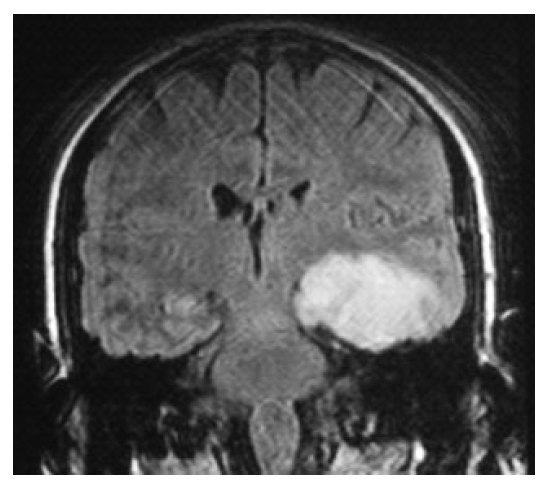

подсказка это состояние вызвано вирусом

Зостером

Может вирус ветряной оспы,но должны быть менинг.симп

идентичен с грпес вирус возбудитель